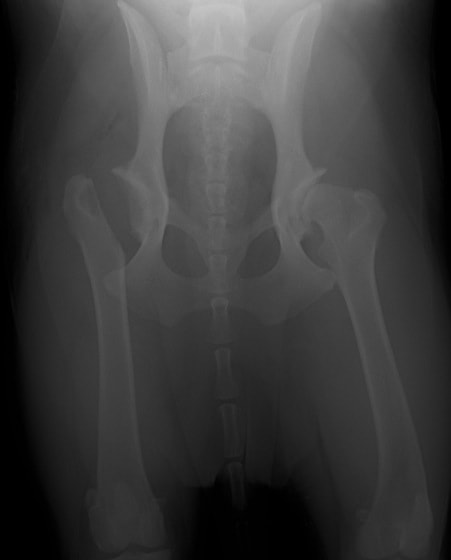

PennHIP法(ストレスX線撮影法)

股関節の緩みを客観的に評価することが可能です。University of Pennsylvania Improvement Program (PennHIP) に評価を依頼する方法です。この機関に依頼する場合、Penn HIP により認定されている獣医師により撮影された特別な撮影像が必要となります。当院では、PennHIP 認定獣医師の資格がありますので撮影が可能です。4ヵ月齢から評価可能ですので、股関節形成不全の発症の有無を知りたい場合にも利用可能です。(PennHIP法の詳しい説明はコチラ)

PennHIP法を実施した症例のレントゲン写真